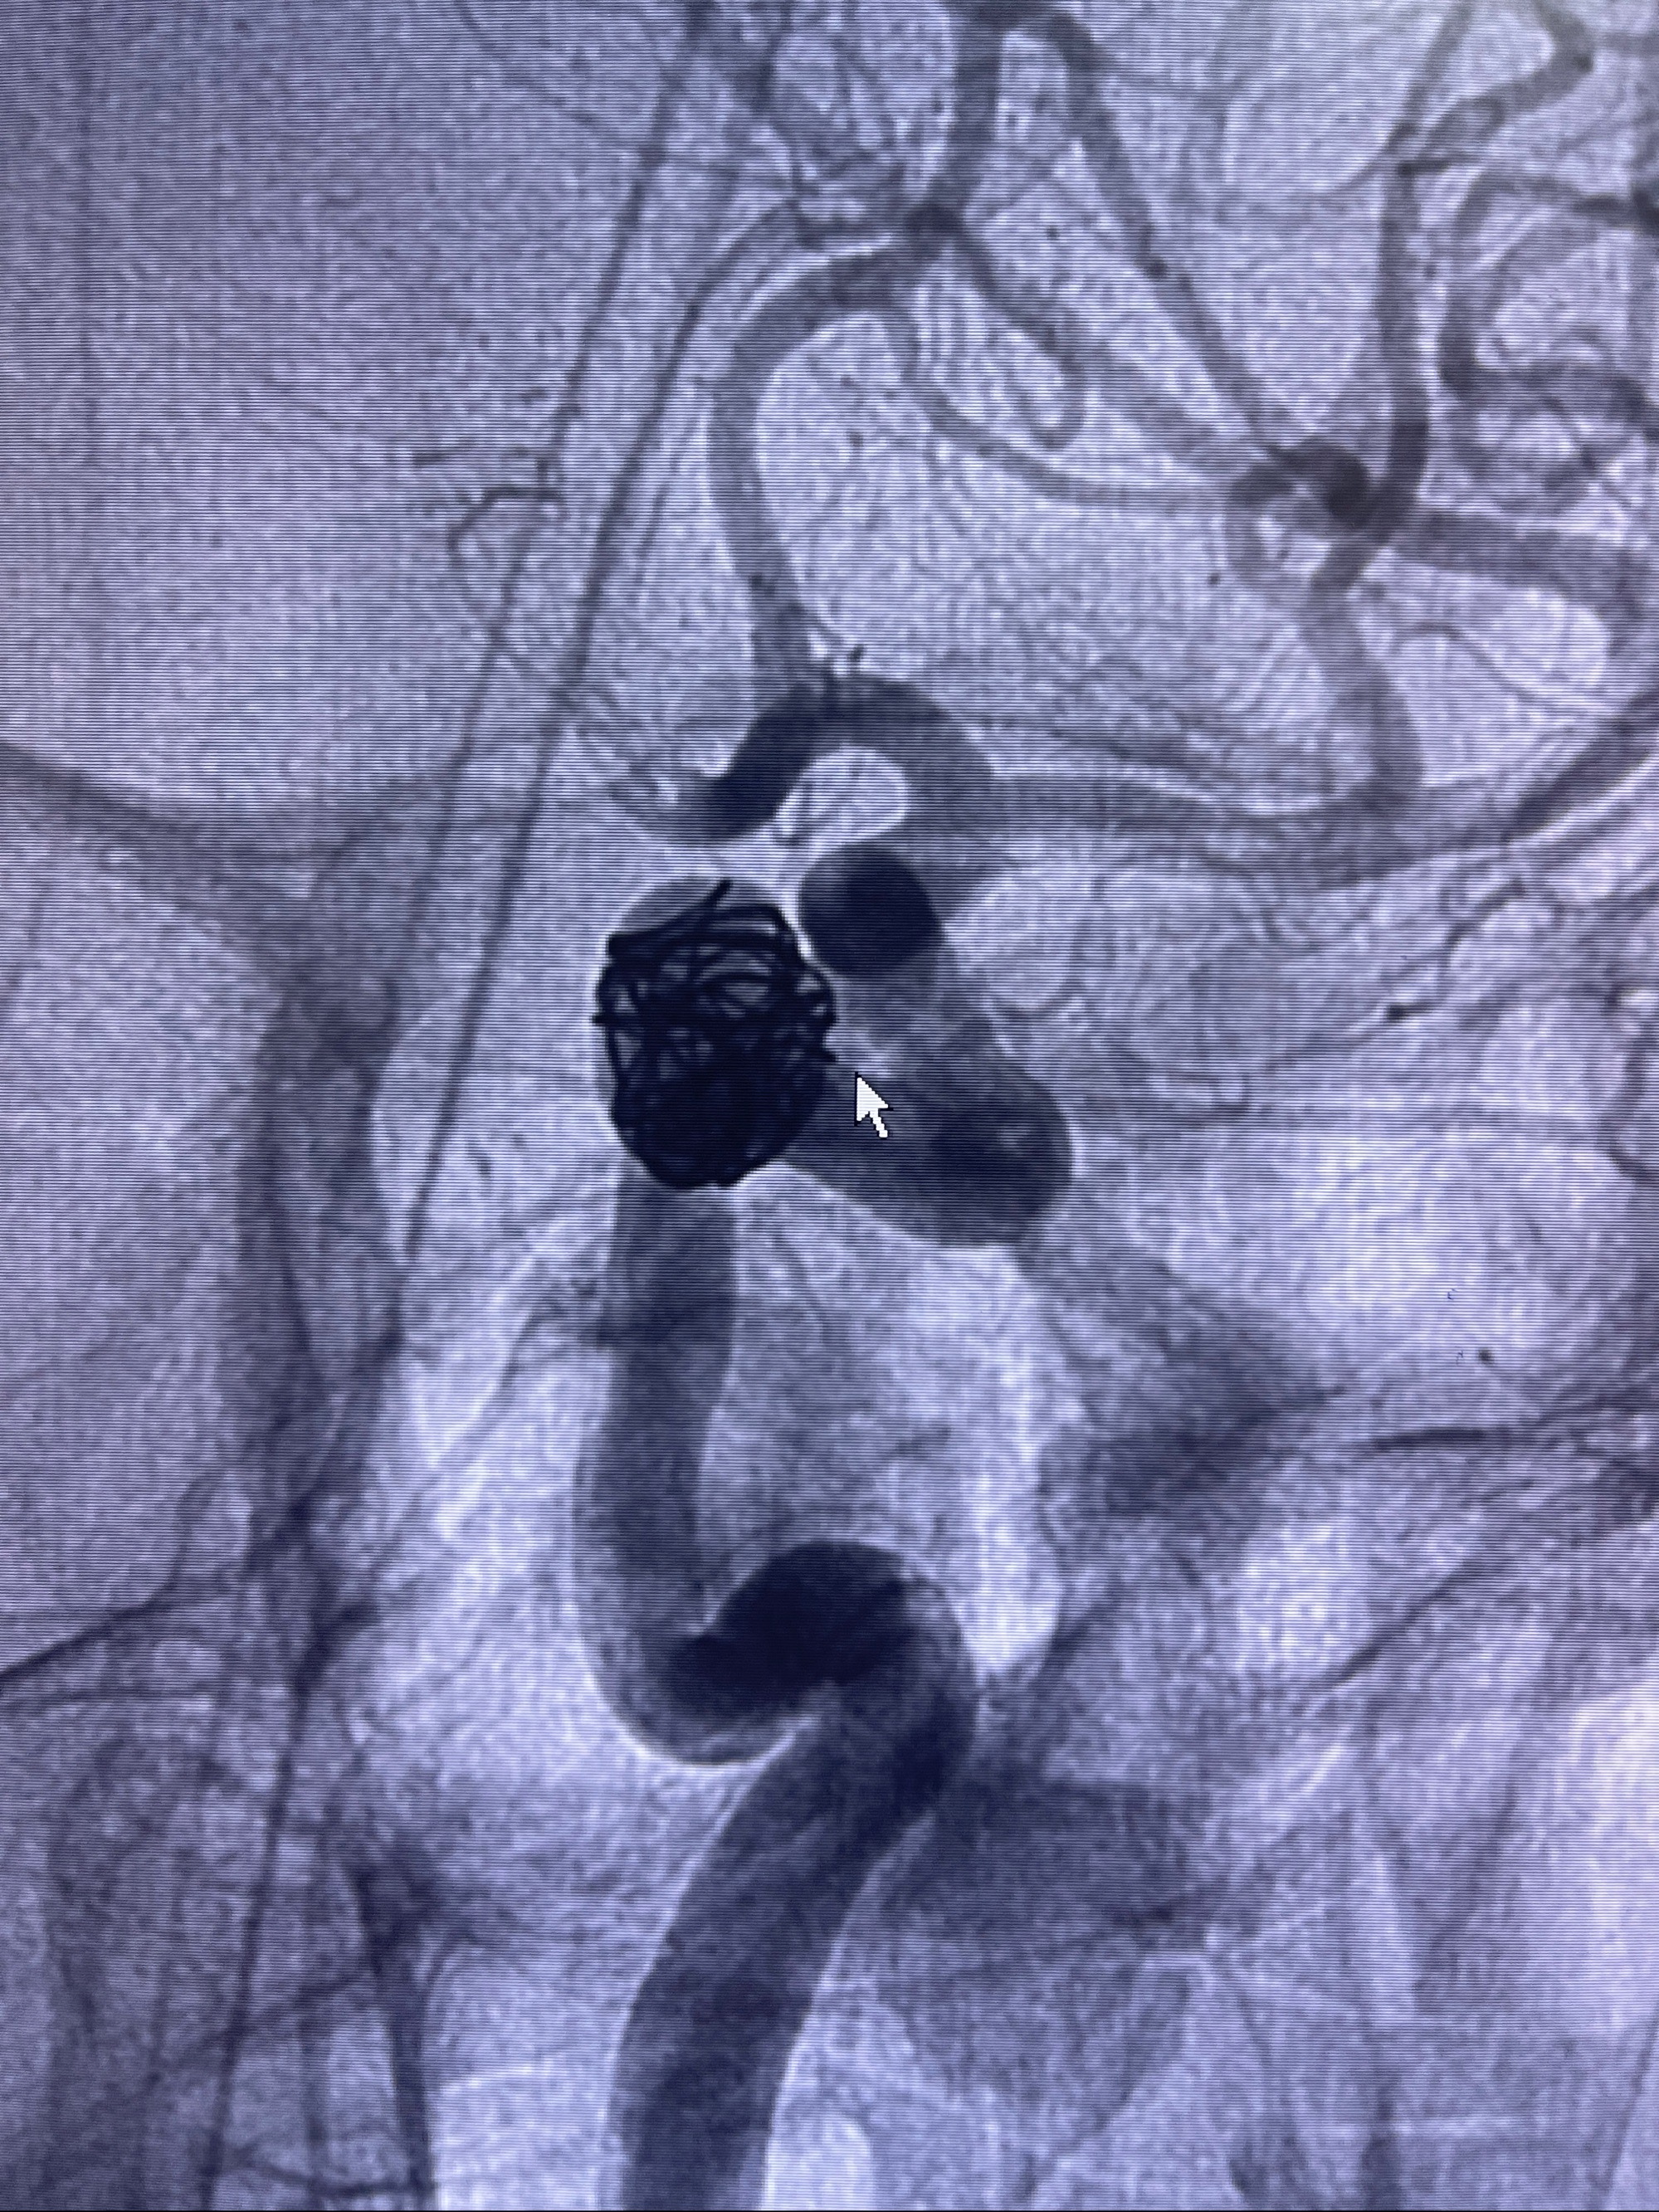

2023-08-30DSA:左侧颈内动脉眼动脉动脉瘤,约3*9.2*7.3mm大小

密网支架辅助栓塞

- Tubridge 4.0-20mm密网支架

- 加奇微弹簧圈:7*30/6*20/5*20/2*8

术后3D显示支架贴壁佳